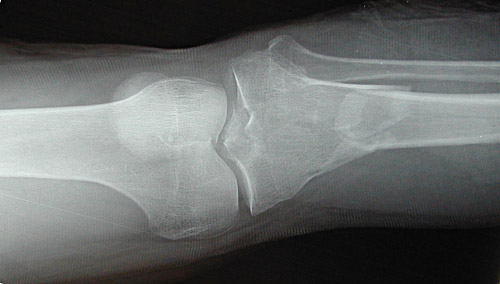

| The radiograph above reveals a highly comminuted spiral fracture of the proximal tibia with downward displacement of the tibial plateau. This was the result of a high speed vehicular accident. In the view below, the fracture has been stabilized with open reduction and internal fixation (ORIF). Staples close the incision. |